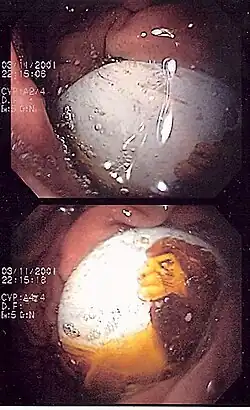

One death and four serious injuries led to the recall of 3.8 million Magnetix building sets in March 2006. The magnets inside the plastic building pieces could fall out and be swallowed or aspirated.[39] In 2009, Luigi Avolio and Giuseppe Martucciello published in The New England Journal of Medicine documenting the effects of magnetic toys ingestion in two children.[40] Since then MEGA Brands has implemented design enhancements to Magnetix, including sonic welding of panels, 100% inspection, gluing magnets into rods, elimination of 3+ labeling in favor of 6+ labeling after it assumed operational control of Rose Art on 1 January 2006. Only safe and improved products are currently on store shelves.[41]

- ^ Avolio, Luigi; Martucciello, Giuseppe (2009). "Ingested Magnets". New England Journal of Medicine. 360 (26): 2770. doi:10.1056/NEJMicm0801917. PMID 19553650.